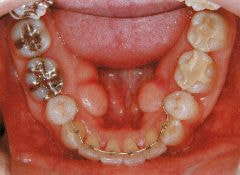

治療例1 (インプラント補綴+矯正)